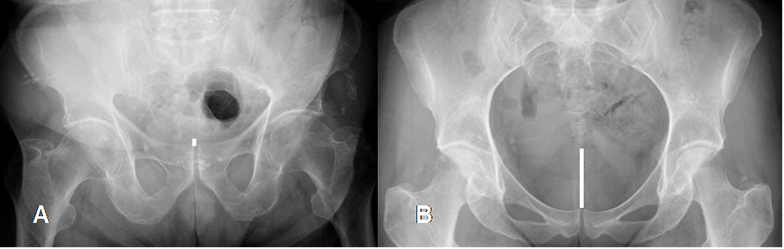

Fig 8. Técnica radiológica. Inclinación pélvica.

Rx AP. A: Disminución y B: Aumento de la distancia sacropúbica, por variación en la inclinación pélvica.